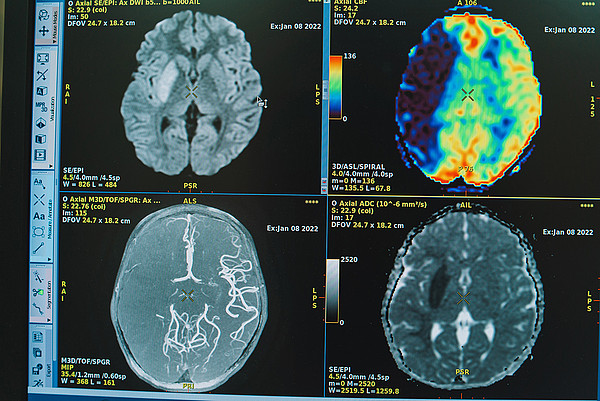

Врачи детской областной больницы спасли семилетнюю девочку с ишемическим инсультом